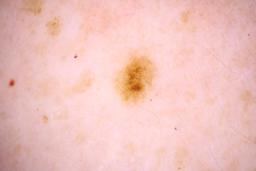

Evaluation set from the ML challenge: SIIM-ISIC Melanoma Classification.